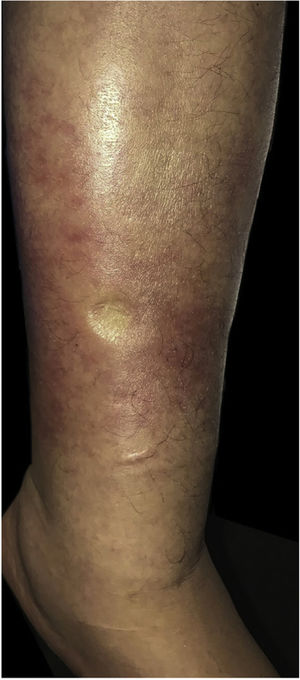

Durante a internação por bacteremia secundária à infecção do trato urinário, foram observadas placas eritematosas com bordas difusas e discreta descamação superficial assintomáticas na superfície anterior e lateral da perna esquerda (figs. 1 e 2).

A infecção por Prototheca varia de envolvimento indolente e localizado da pele, infecção de tecidos moles, bursite do olecrano em pacientes imunocompetentes, a infecção disseminada devastadora com algemia e infiltração visceral com alta mortalidade em hospedeiros imunocomprometidos em decorrência de transplante, diabetes, HIV e doenças hematológicas.2,3 A forma cutânea representa a manifestação mais frequente (três em quatro pacientes). As lesões geralmente aparecem em áreas expostas à implantação traumática. Em geral, apresenta‐se como placas eritematosas mal definidas, embora com menos frequência possa se manifestar como lesões nodulares, pustulosas, verrucosas e ulceradas.